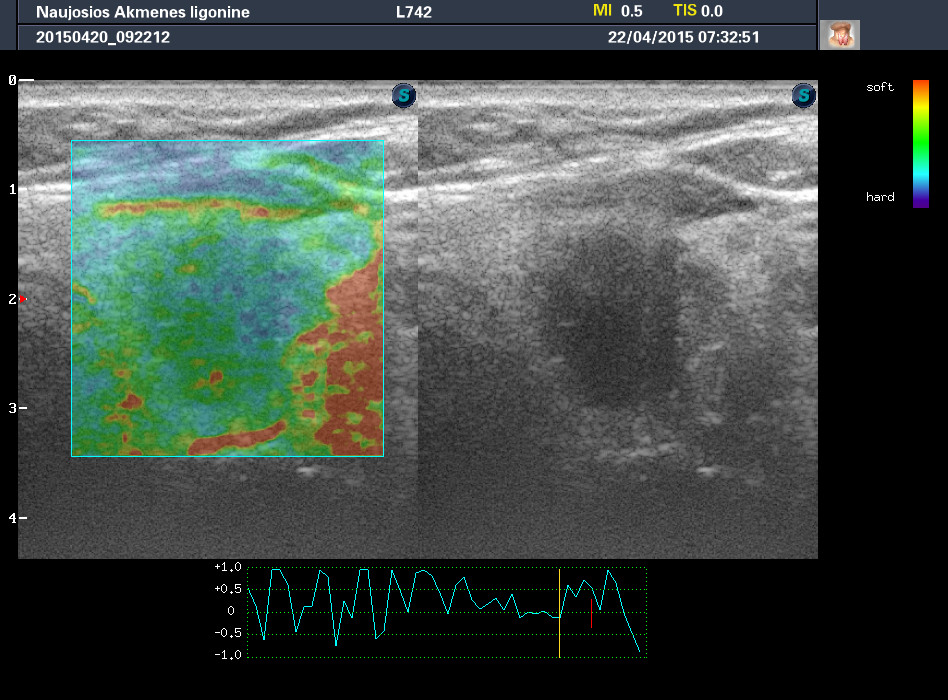

Случай 2

Женщина 61 год, жалоб нет. Рост узла за год +1 мм. Регионарные ЛУ не увеличены.

apr222015113413_30.jpg

1-й узел злокачественный, а 2-й ,скорее всего, доброкачественный. Но,понятное дело, нужна пункция и было бы здорово узнать результат.

Mattiola писал(а): И,простите, что за исследование на сканах, не на видео? Я такого не делаю и,к сожалению, не знаю,как интерпретировать его(

Эластография. http://www.medison.ru/si/art380.htm